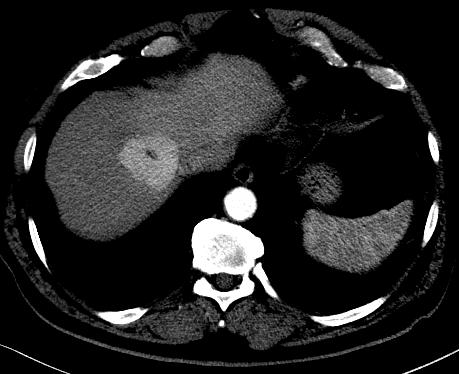

CT will show FNH as a vascular tumor, that will be hyperdens in the arterial phase, except for the central scar.

Above a typical FNH with a central scar that is hypodens in the portal venous phase .

The key to the diagnosis in the lesion on the left is the fact that it is isoattenuating to normal liver in the portal venous phase and stays that way without a wash out on the delayed phase